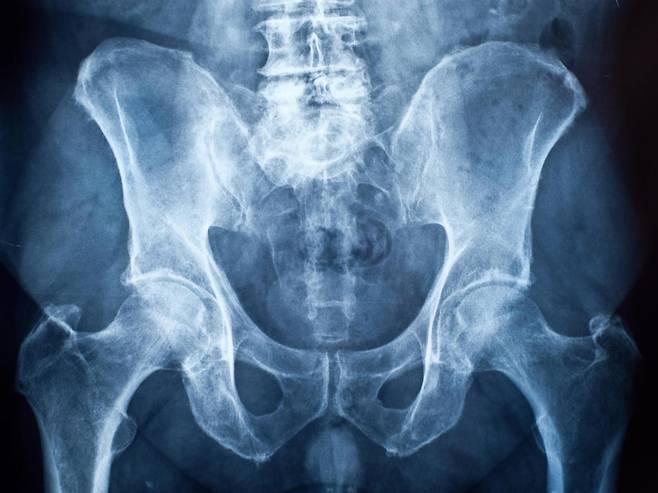

![인체를 X선 촬영하면 성기에 뼈가 없다는 사실을 알 수 있다 [Independent]](https://img1.daumcdn.net/thumb/R658x0.q70/?fname=http://t1.daumcdn.net/news/201612/15/joongang/20161215165644939ujmj.jpg)

진화론에 따르면 생물은 생존에 유리한 방향으로 진화한다. 보다 잘 번식할 수 있는 방향으로 진화하는 현상을 ‘진화적 적응’이라고 한다. 그런데 인간의 생식기는 이런 ‘진화적 적응’을 벗어난 것처럼 보인다. 인간 생식기에는 뼈가 없어서다.

인간은 단단하고 큰 생식기를 만들겠다며 정력제나 보양식을 먹기도 한다. 그런데 인간의 생식기는 스펀지 같은 해면체 조직이 성적 자극을 받을 때만 단단해지는 형태로 진화했다. 왜 인간의 생식기는 번식에 유리하지 않은 방향으로 진화한 것일까?

영국 유니버시티칼리지런던(UCL)의 학자들은 대부분의 영장류 수컷이 생식기에 뼈를 갖고 있지만, 인간은 예외라는 점에 주목했다. 세계적으로 저명한 학술지 사이언스(Science)가 14일(현지 시간) 이 계통분류학자들의 연구를 소개했다.